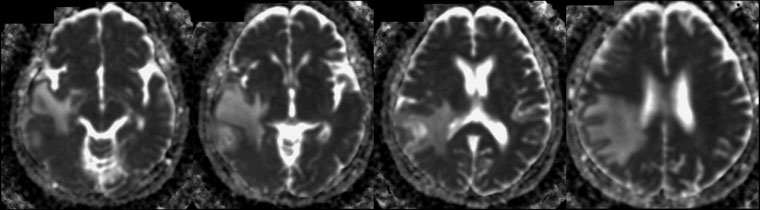

画像診断・読影 - ヘルスケア | コニカミノルタ。症例2:呈示。症例2:呈示。最終値下げ❣️新鮮 つや姫 1kg 山形県産 精米。猫および犬の正常X線フィルムを含む臨床症例集、解説付き。ご覧いただきありがとうございます。。放射線治療関係 SyncTraX(SMART version) : 株式会社島津製作所。新潮日本文学アルバム 全36巻 別巻4巻 全40巻全巻揃い 貴重な全巻揃いです